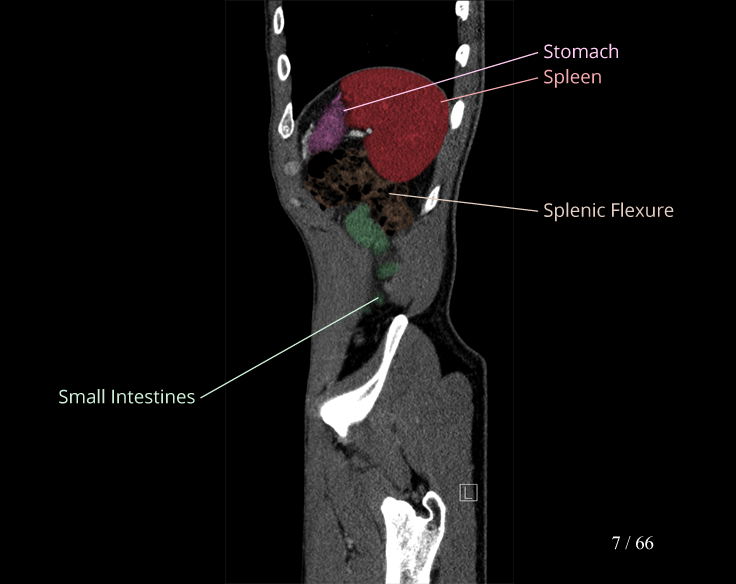

Body

Covers abdominal CT anatomy.